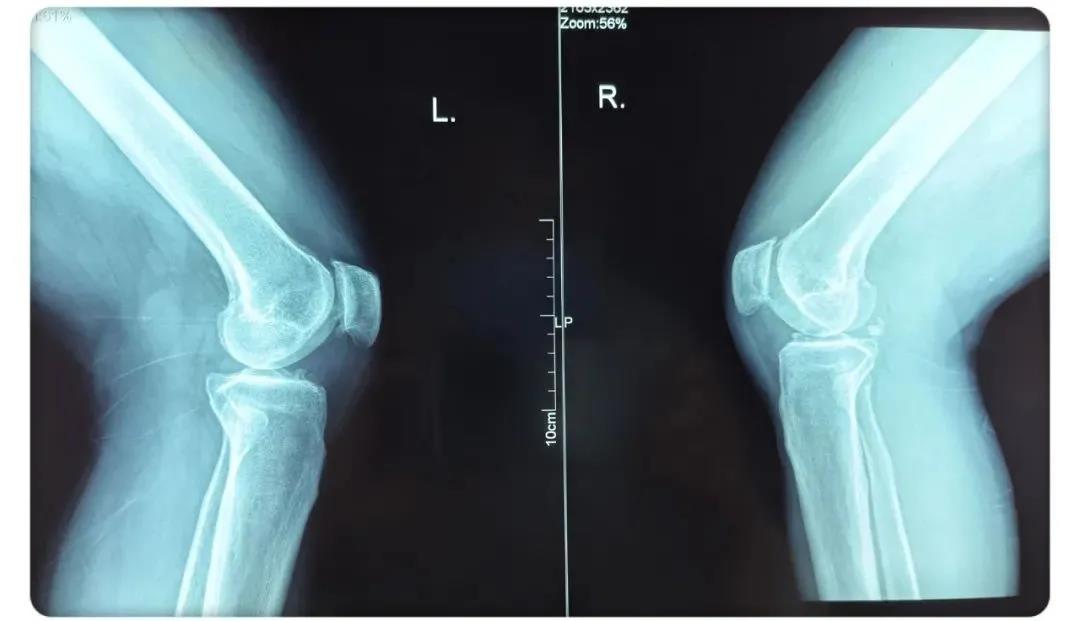

術(shù)后患者膝關(guān)節(jié)側(cè)位片

術(shù)后患者膝關(guān)節(jié)正位片